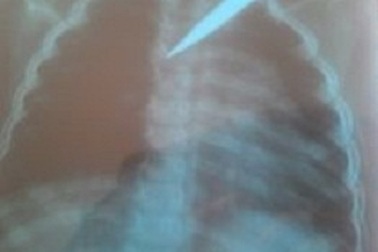

BV Nhi Đồng 1: Cấp cứu kịp thời cứu bé 5 tuổi bị kéo đâm xuyên ngựcCác bác sĩ khoa Cấp cứu Bệnh viện Nhi đồng 1 TP.HCM vừa tiếp nhận cấp cứu cho một cháu bé 5 tuổi nhập viện trong tình trạng bị kéo đâm xuyên ngực.